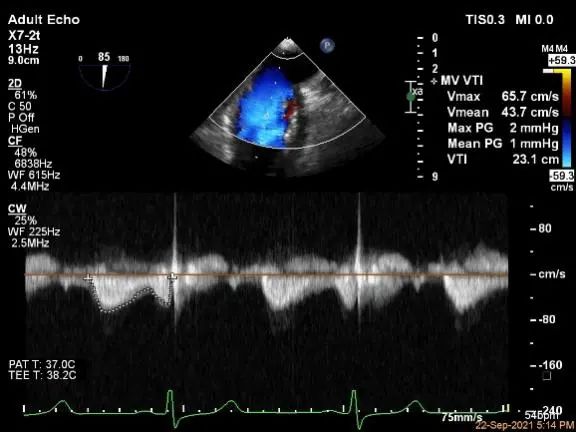

评估瓣口条件,平均跨瓣压差:2mmHg,决定在第一个夹子外侧下第二个夹子

评估瓣口条件,平均跨瓣压差:4mmHg

评估二尖瓣瓣口平均跨瓣压差:1mmHg